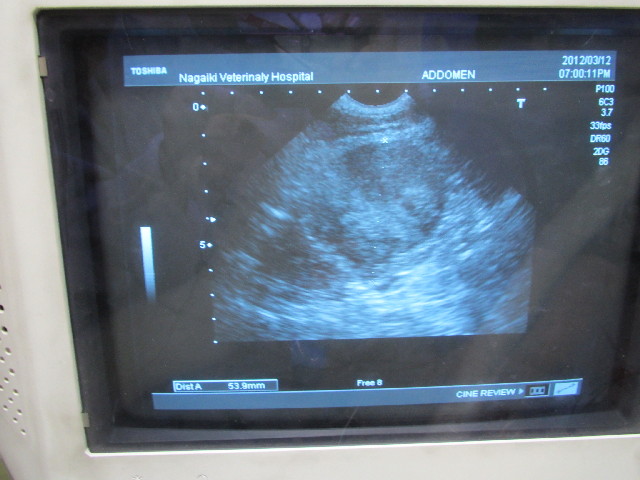

今日はべべちゃんの右の腎臓の移行上皮癌の大きさを2週間に一度エコーで調べる日でした。

今日のエコーも、べべの右の腎臓に腫瘍があるのを発見したN先生です。

結果としては最大直径が53mmで、2週間前1ミリほど大きくなっていました。

.....という事は月に5ミリのペースをグンと落とす事ができたわけで

この調子なら、月に2ミリ大きくなる計算なので....そのくらいかそれ以下に抑えられたらいいよね!!